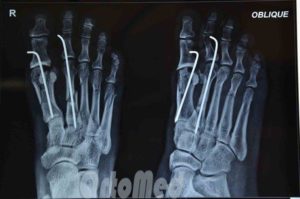

Хирургические методы лечения назначаются при осложненных переломах со смещением и предполагают госпитализацию пострадавшего. В ходе операции через ногтевую фалангу пациента вводится специальная спица, способствующая скелетному вытяжению обломков.

В наиболее тяжелых случаях проводится хирургическое вмешательство под действием общего наркоза. Кисть разрезается, проводится вправление и сопоставление костных фрагментов. Специалист придает кисти и пальцам правильное положение, после чего вводится спица. В завершение операции накладываются швы и фиксирующая гипсовая повязка.

При любом переломе, а особенно 5-й плюсневой кости, осуществляется рентгенография стопы в 3-х проекциях: боковая, переднезадняя и косая.